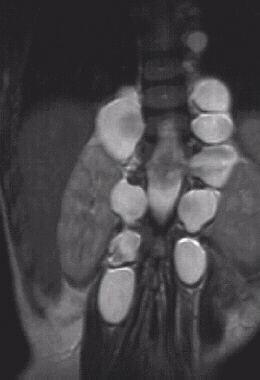

This 7 year old male presented to the cerebral palsy clinic with mild development delay, hyperactivity, and kyphosis. On physical examination he was slightly small for age (5th percentile weight for age, 10th percentile height for age) and had hyperactivity. He had no clonus or spasticity but a slightly clumsy gait. An MRI and plain x-rays were ordered (image 1, 2 & 3). After two years of brace wear the kyphosis increased to 78 degrees(image 4). The child is complaining of the brace and starting to refuse brace wear.

A change in treatment is indicated because the curve is increasing and switching to a body cast would be the next stage.

If surgery is to be considered an anterior release and posterior fusion would be required.

The fusion and instrumentation of the kyphosis should extend to T12.